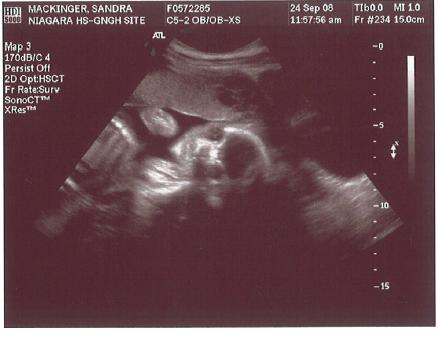

22. Schwangerschaftswoche:

Ein Nickerchen in Ehren ...